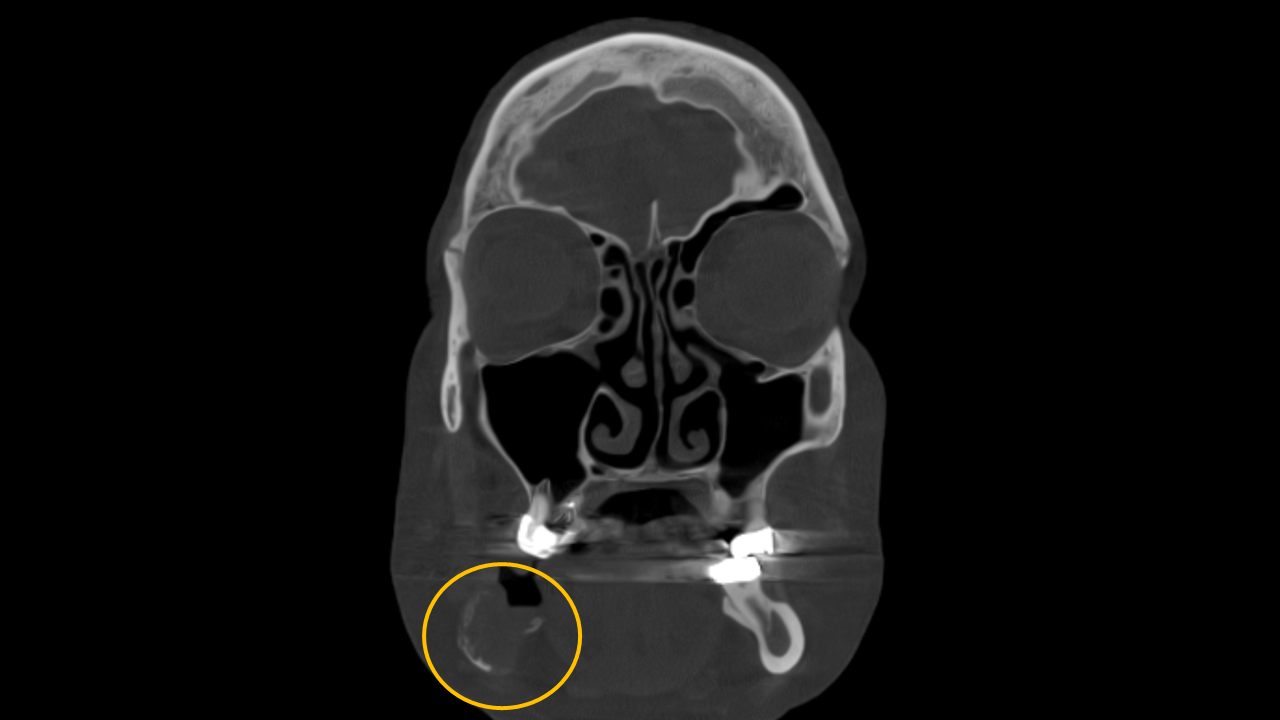

Study 4

Finding: A mixed-density lesion is observed at the mandibular arch, characterized by varying levels of internal radiodensity surrounded by regions of low-density. The lesion has caused expansion and resorption of the adjacent cortical plates. No root resorption is detected in the associated teeth. These imaging findings are indicative of florid cemento-osseous dysplasia.